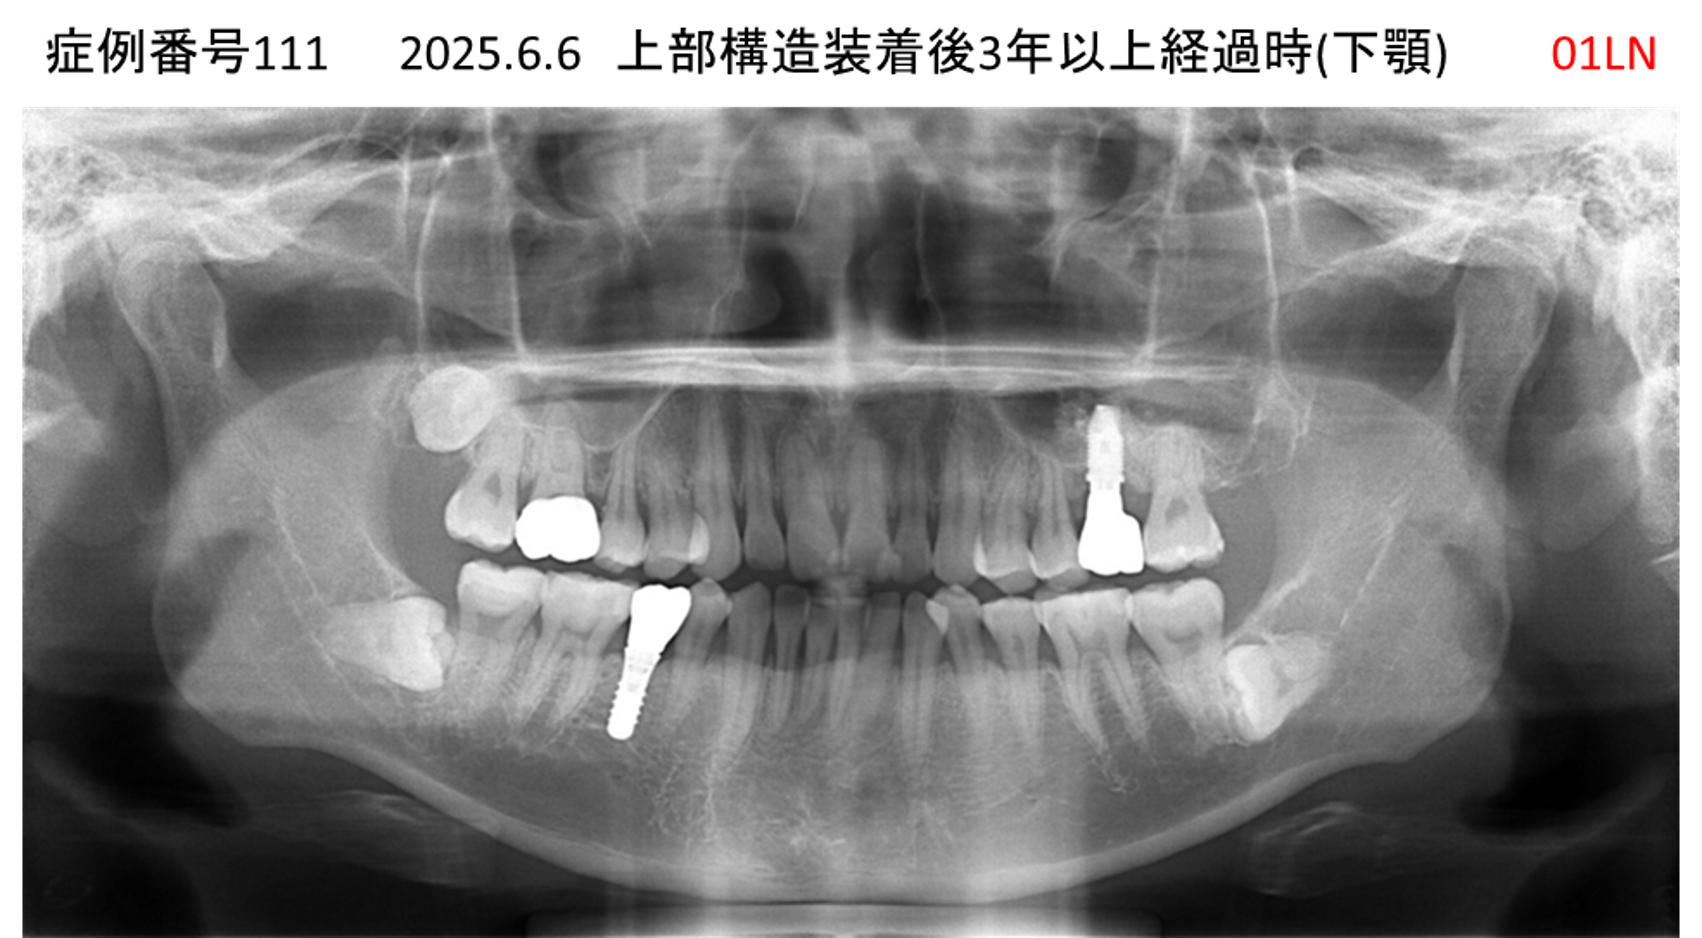

左下の奥歯が痛い患者様のインプラント症例

| 治療名称 |

インプラント |

| 治療費用 |

215万円+税 |

| 治療期間 |

5か月 |

| 患者さんの症状(主訴) |

左下の奥歯が痛い。 |

| 治療内容 |

| 治療結果 |

痛み無く、噛める。 |

| 治療の注意点(リスク/副作用) |

インプラントが壊れたら再治療が必要 |